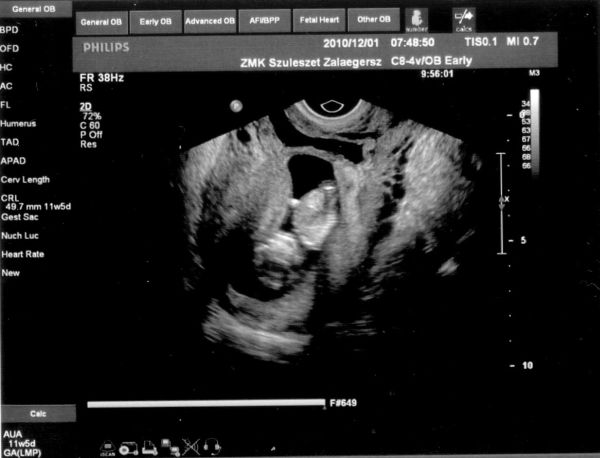

Kép 11. heti ultrahang